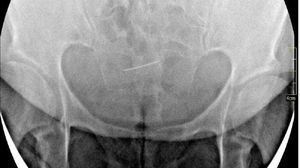

Femeia a fost dusă la spitalul Sf. Spiridon, acolo unde cadrele medicale care au îngrijit-o au descoperit „un ac medical care a migrat între oasele bazinului”.

Chinul femeii a început în anul 1990, atunci când a fost operată din cauza unei sarcini extrauterine cu peritonite. În timpulintervenției chirurgicale, dr. Doina Ianca, de la Maternitatea „Elena Doamna”, i-a extirpat o trompă și un ovar, dar a uitat un ac în abdomenul pacientei. Femeia a început să se simtă rău, din senin, după mai mulți ani.